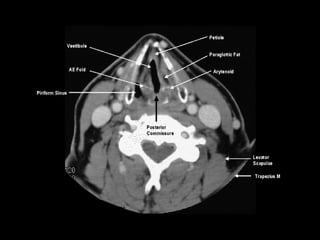

Radiographers use medical imaging equipment like X-rays and MRIs to produce images of patients' internal structures and organs. They are responsible for positioning patients, operating scanning machines, and ensuring quality images. Radiographers must have strong attention to detail, excellent communication skills, and the ability to work well under pressure to accurately capture anatomical features and diagnose any abnormalities.